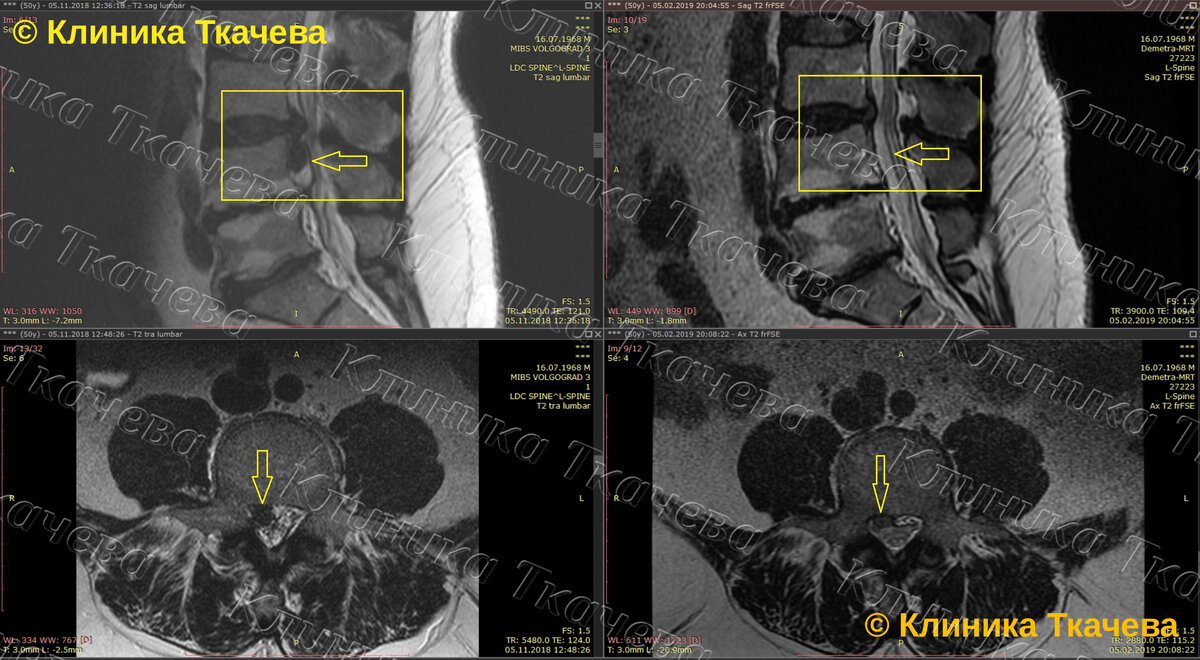

Диагноз: межпозвонковая грыжа L3-L4 с наличием секвестра, который сместился вправо и каудально (вниз). Вертикальный размер секвестра - 2 см, горизонтальный - 1 см.

Результат: 100% резорбция секвестра и почти полная резорбция грыжи!

В настоящее время жалоб нет. Время резорбции - 2,5 месяца после лечения!!!  #РЕЗОРБЦИЯ_РУЛИТ

МРТ-снимки: 5.11.18. - 5.02.19.